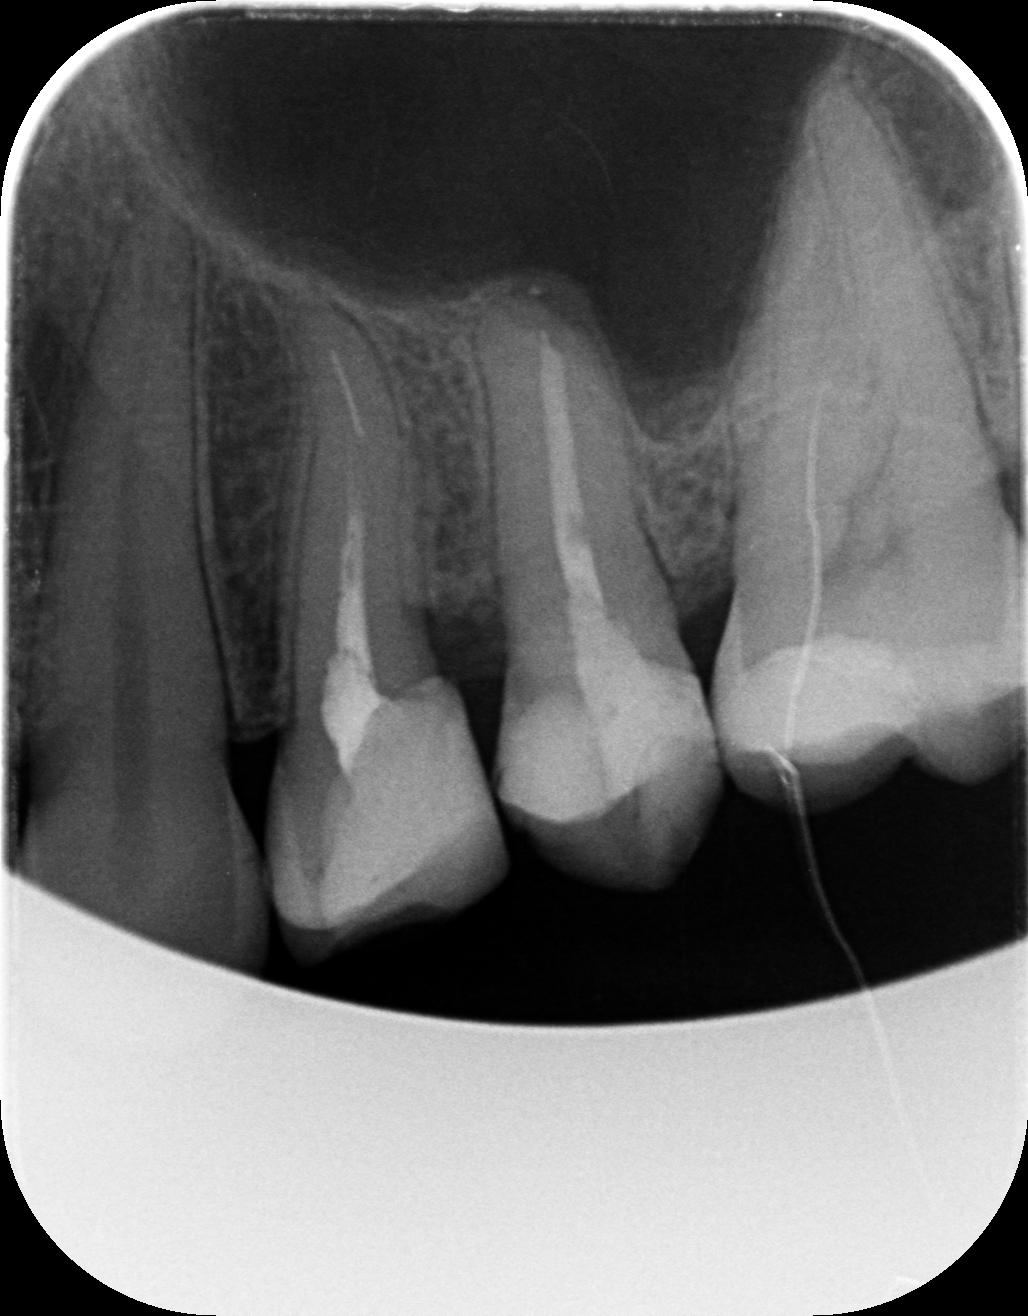

Dantų kanalų gydymas